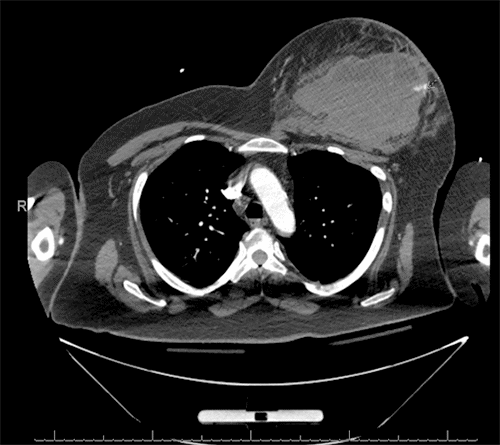

A 50-year-old female with a history of obesity (BMI 43.7) and Factor V Leiden deficiency with prior pulmonary emboli presented following a low-speed motor vehicle collision as a restrained passenger. She developed a large left breast hematoma confirmed by imaging (Figure 1). CTA revealed a 10 × 12 cm hematoma with active bleeding from an arterial branch along the anterolateral chest wall (Figure 2). The bleeding source was suspected to be either the lateral thoracic artery or the pectoral branch of the thoracoacromial artery. Notably, she was on rivaroxaban, a blood thinner, with the last dose taken approximately 18 hours before presentation.

Figure 2. Left Breast Hematoma Measuring 10 × 12 cm. Published with Permission

Active arterial extravasation from a branch coursing along the anterolateral chest wall